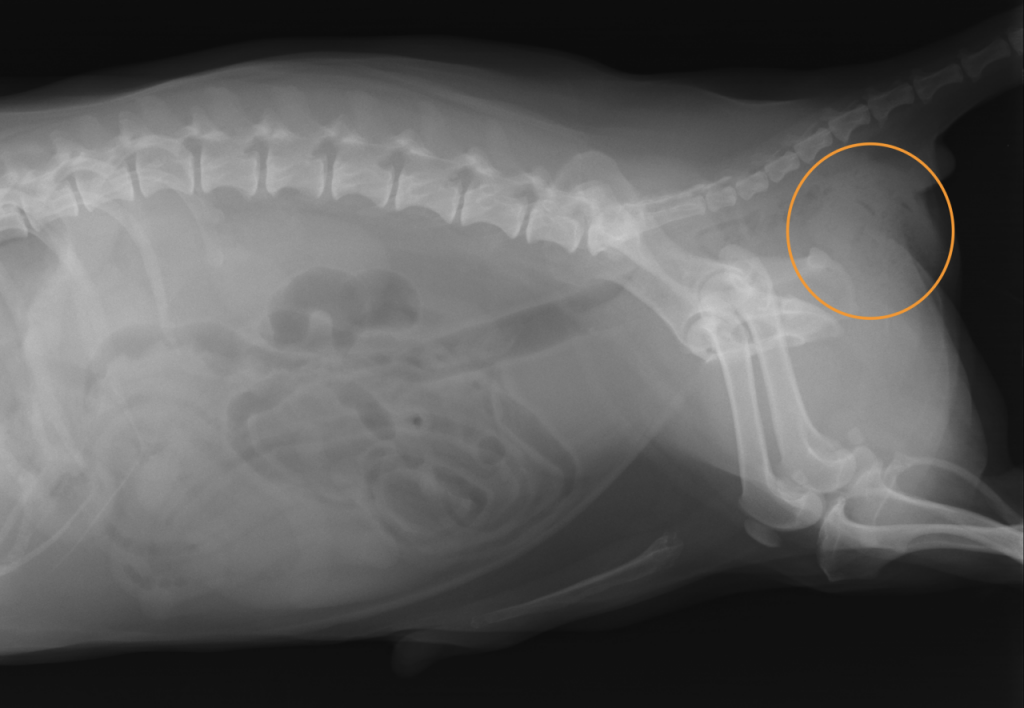

レントゲンでは、下写真のマークした部分に便の貯留が見られました。

(造影剤をお尻から注入するとレントゲンで白く写り、便の溜まりが見えやすくなります。)